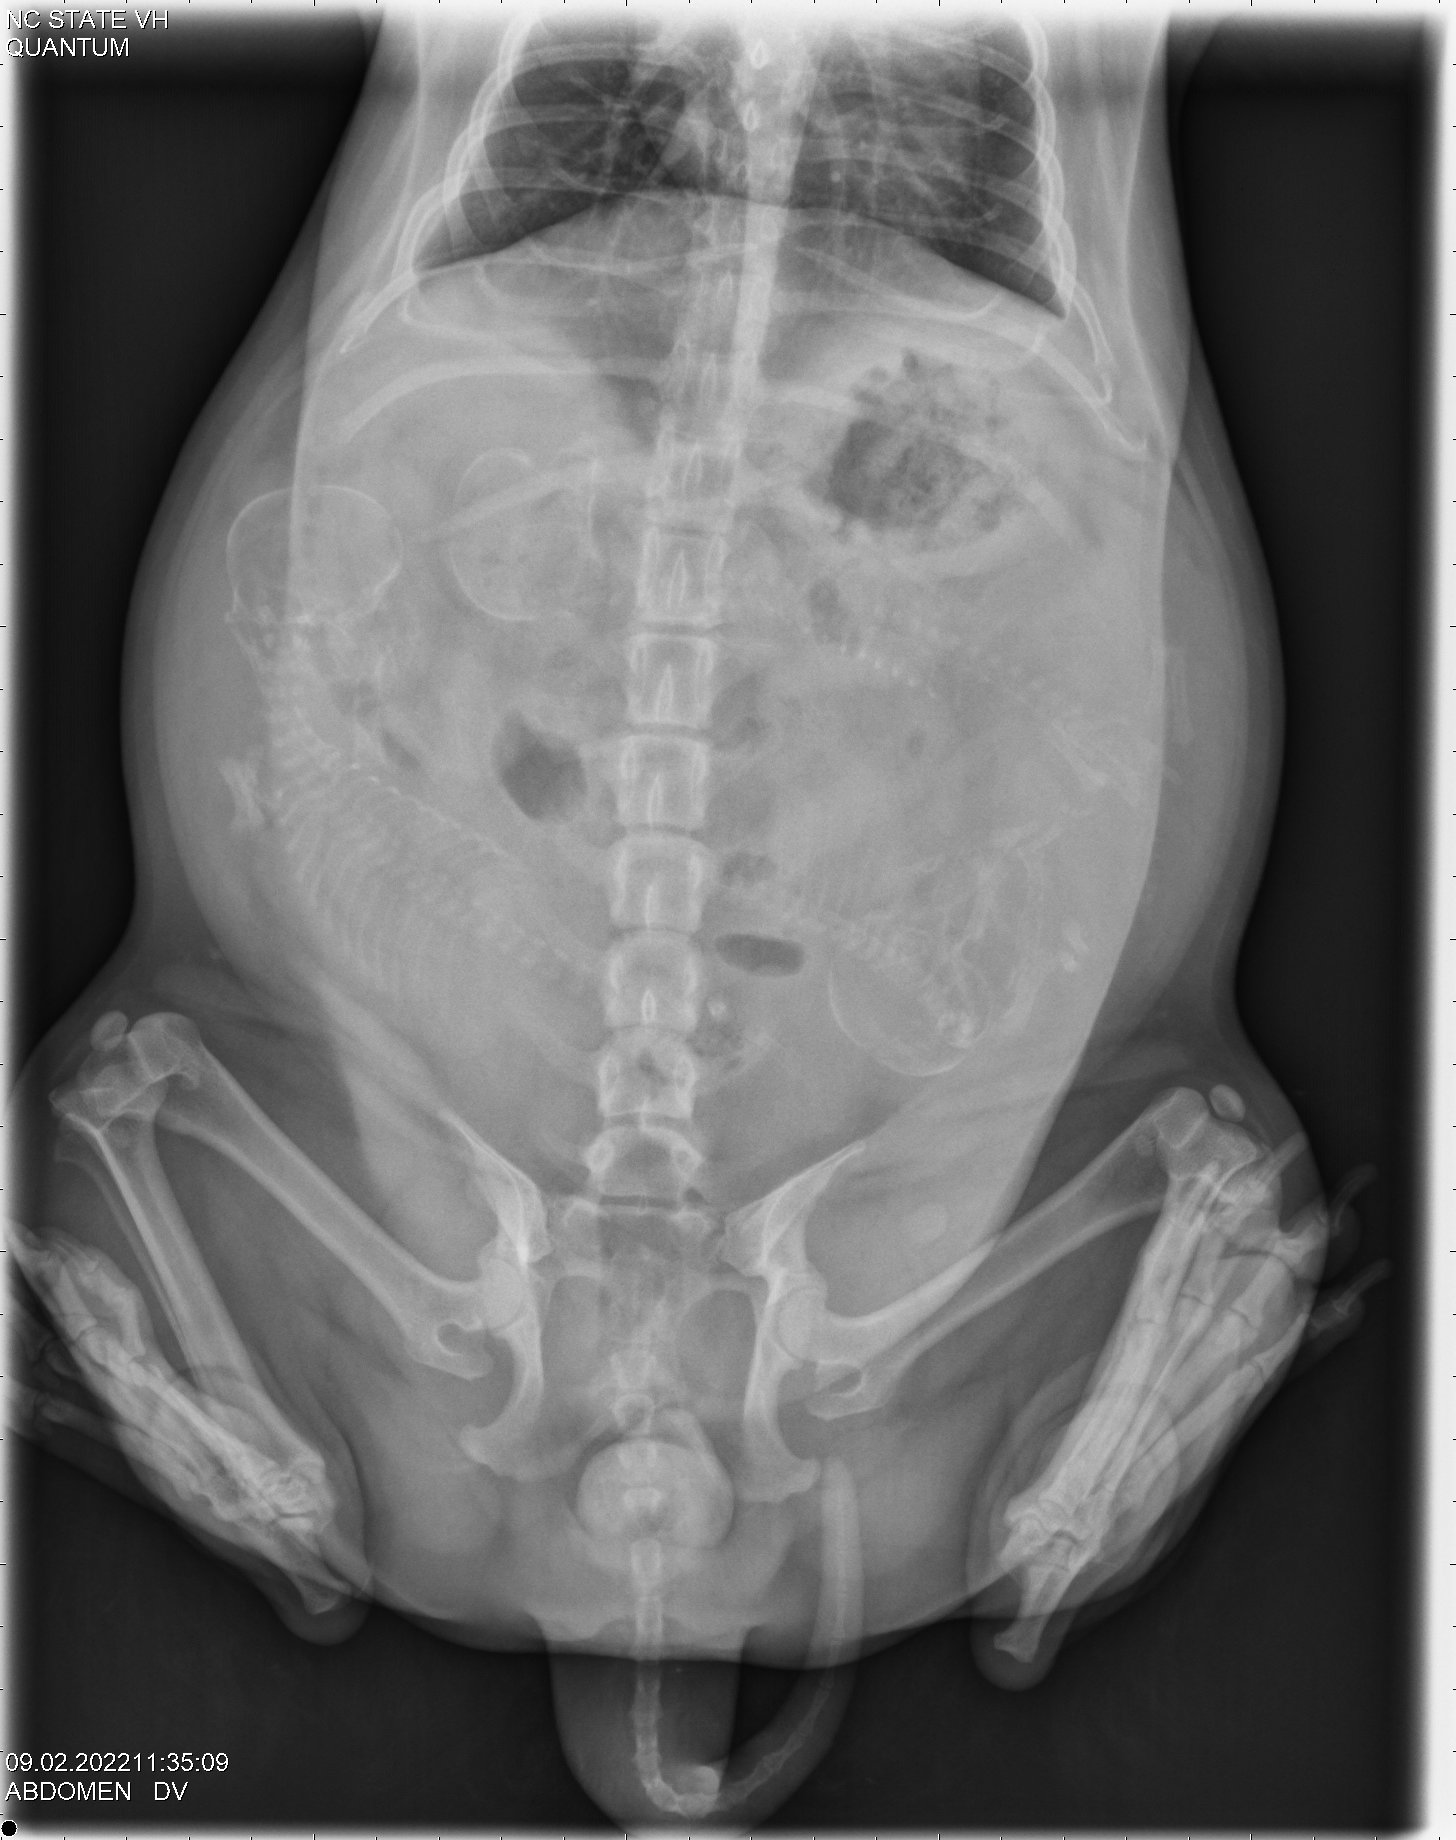

Today was x-ray day! Because ultrasound is so unreliable in counting the number of puppies, late in a canine pregnancy my repro vets at NC State University take an x-ray to get an accurate count of the number of puppies. Boo is carrying three puppies! (The mean average size of a Norwich litter is 2.7.)

Here are the x-ray pictures:

Using the x-ray, by comparing the size of the puppy skulls and the size of Boo's pelvic opening, the vets are also able to give a recommendation as to whether Boo needs a cesarean section (c-section) or if I should let her try to give birth to the puppies. Unfortunately the puppy skulls are almost the same size as Boo's pelvic opening, so the recommendation is that Boo should have a c-section. So this is what we will do.